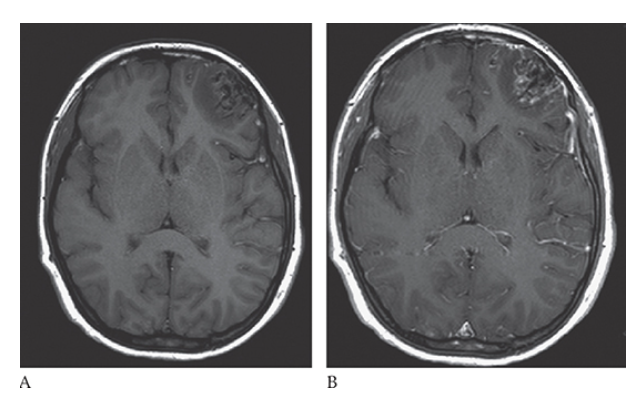

What is A

Meningioma. T1-weighted axial MR image shows an isointense left parasagittal meningioma and postcontrast T1-weighted images in the axial

What is B

Meningioma. T1-weighted axial MR image shows an isointense left parasagittal meningioma coronal

What is C

Meningioma. T1-weighted axial MR image shows an isointense left parasagittal meningioma and sagittal

What is D

Meningioma. T1-weighted axial MR image shows an isointense left parasagittal meningioma planes.